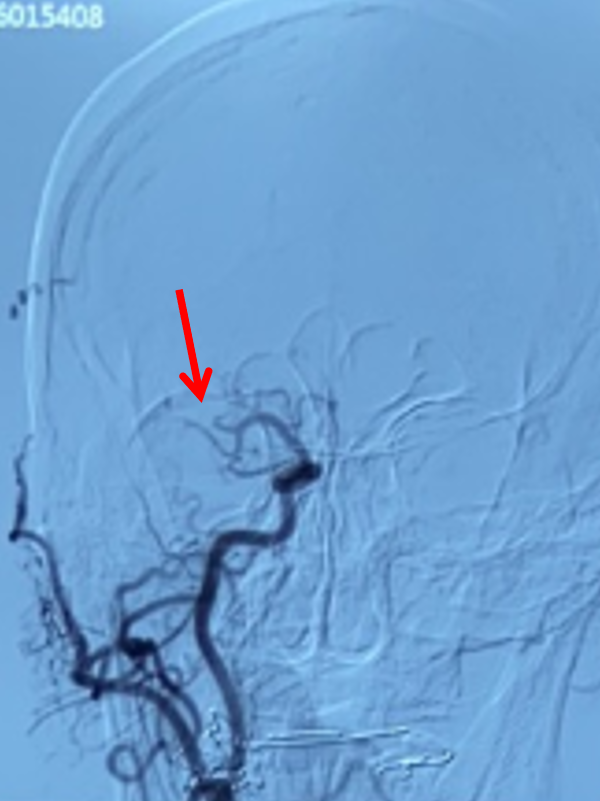

右侧颈总动脉侧位造影:右侧大脑中动脉M2上干、下干均闭塞(箭头示)。